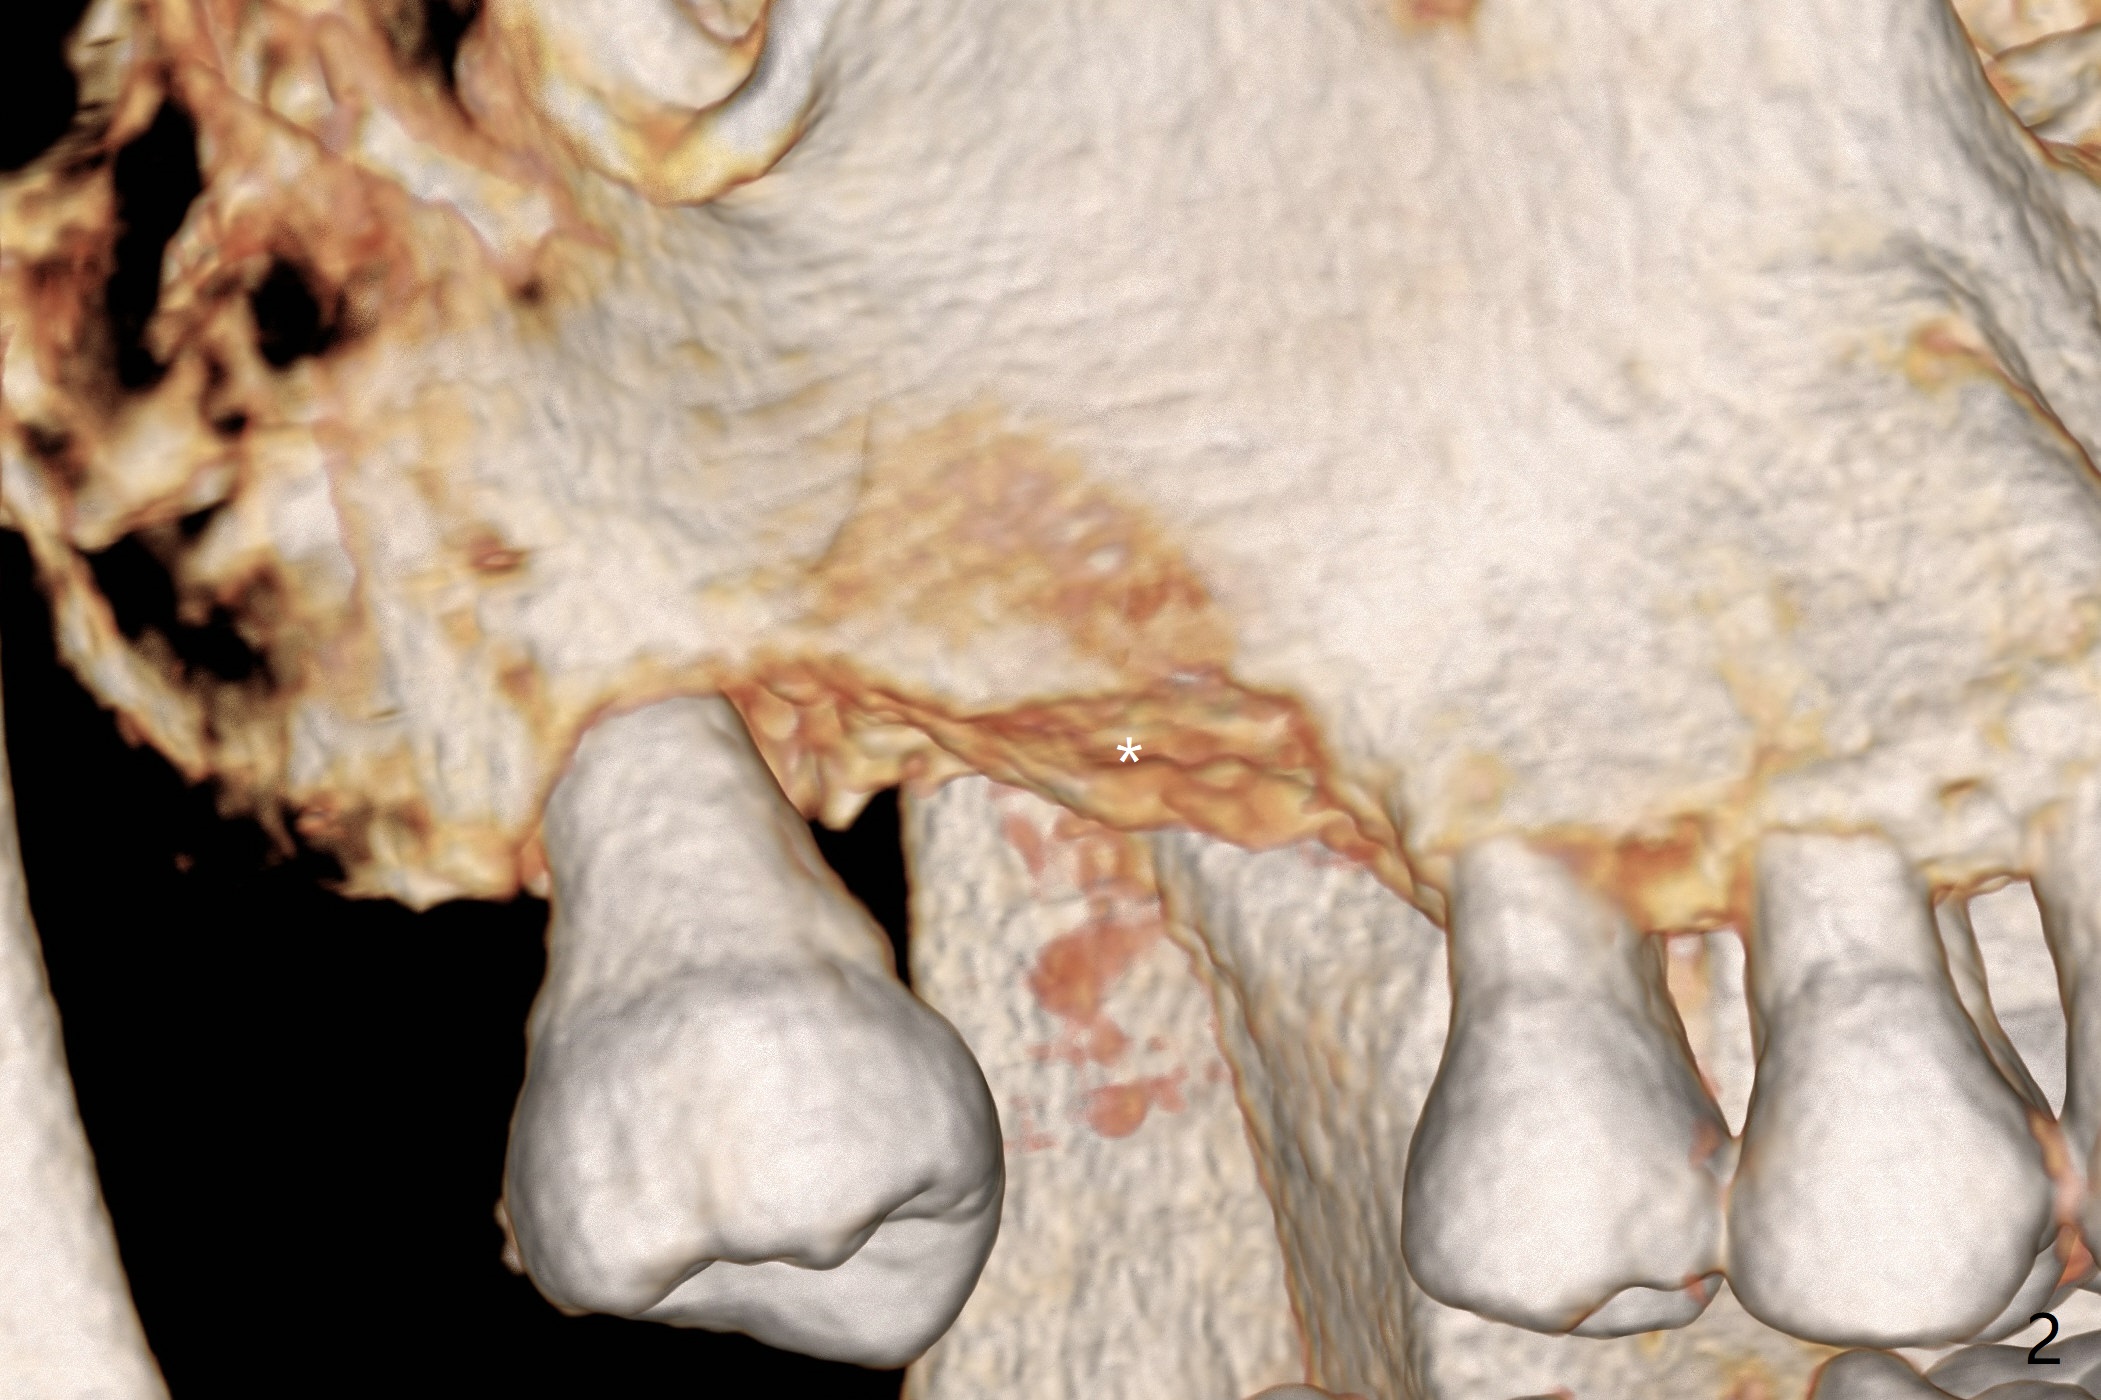

A 43-year-old man has ~ 2 mm bone at #3 (Fig.1). To reduce sinus membrane perforation and abutment screw loosening, a shorter, but larger Magicore will be used (5x7(3)) if an implant is to be placed at the same time of bone graft. Since the crestal bone is loose (Fig.2 *), internal sinus lift is feasible with Magic Sinus Lifter. Flap surgery will make it easy to place bone graft to increase crestal bone height as well as bone volume surrounding the neighboring teeth. A 6-month membrane will be used for guided bone regeneration (GBR). A spacer will be placed to keep the space and replace a flipper the patient is wearing now. The spacer is favorable for wound healing. PRF membranes will be prepared (x3). External sinus lift seems to be safer (Fig.3 arrow).